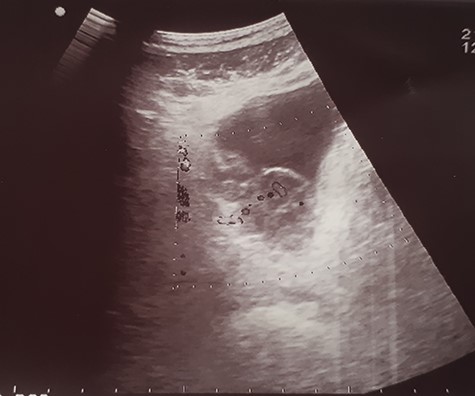

His Hematuria was first explored by abdominal ultrasound, showing an irregular wall thickening in the right lateral face and the floor of the bladder measuring 5 × 3 cm (Fig. 1) with a vascularized appearance (Color Dop and a right hydronephrosis. Computed tomography (CT) scan confirmed ultrasound findings and showed metastatic lymph nodes in both inguinal areas and in internal iliac and latero-aortic areas measuring up to 3 cm and a 4 cm mass in the left adrenal gland (Fig. 2). Digital rectal examination finds a fixed bladder floor. He underwent cystoscopy, which revealed a huge solid non-papillary black pigmented lesion located in the floor and in the right lateral face of the bladder hiding the right ureteral meatus (Fig. 3). Monopolar loop electrocautery was used to excise the tumor as a palliative treatment to stop hematuria. Tumor shavings were particularly blackish (Fig. 4). Pathological examination confirmed the diagnosis of malignant melanoma (Figs 5 and 6). The patient was actually treated with chemotherapy for a metastatic malignant melanoma. Although an evaluation CT scan showed significant progression under chemotherapy of the majority of lymph nodes, our patient is no longer complaining of hematuria or low urinary tract signs.

Ultrasound image showing an irregular wall thickening in the right lateral face and the floor of the bladder.